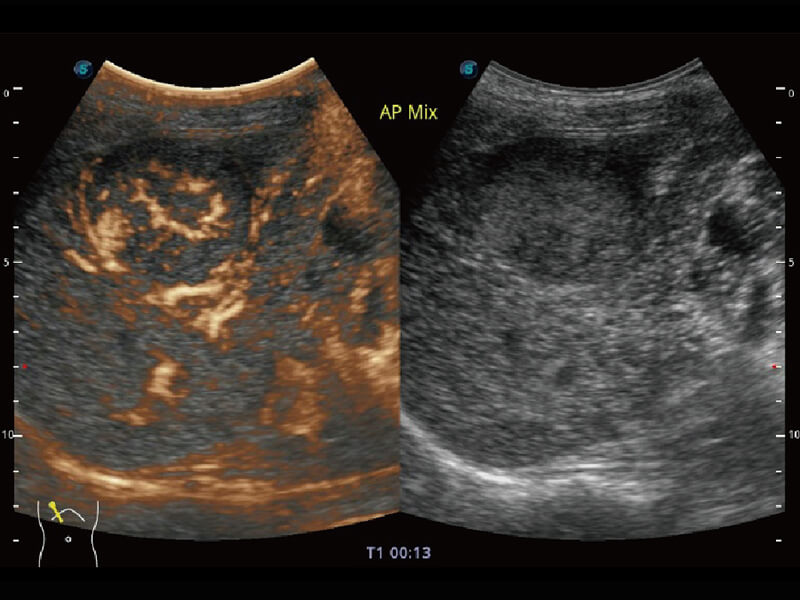

性能优异的硬件架构,极大提升超声系统的运行效率和数据处理能力。相比以往超声成像系统,Wis+平台为您带来极快的响应速度和成像帧频,提升检查流畅度。

超宽频带技术,为容积成像带来优质的二维图像基础,为您呈现丰富的结构细节,栩栩如生地展示宝宝的宫内形态以及各种组织的立体结构。